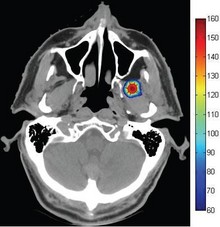

Thermal ablation in the head and neck requires accurate thermal dose delivery to target tissue while protecting the structure and function of nearby tissue and organs. In this study, we present a method that allows importing Computed Tomography (CT) scans to COMSOL, in order to model accurately the expected pathological outcomes prior to thermal ablation treatment.

Thermal ablation of a virtual tumor was performed for a conductive interstitial thermal therapy (CITT) device. Importing images of anatomical structures into COMSOL allows for a reliable model of heat distribution during thermal ablation of targeted tissue.